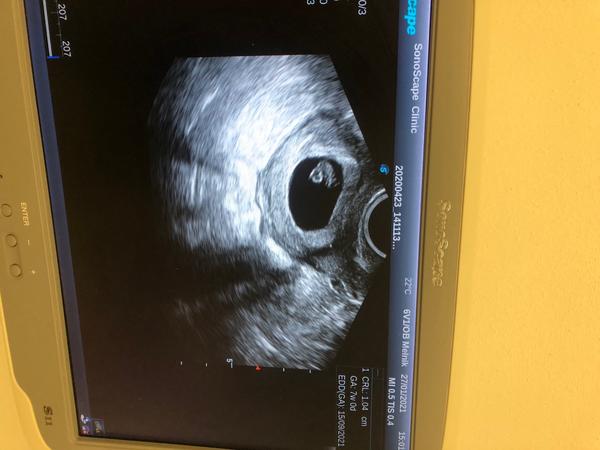

Děvčata dnes jsem byla na kontrole. A vše v pořádku🥰 miminko je tam kde má být🤗 tluče i srdíčko❤️